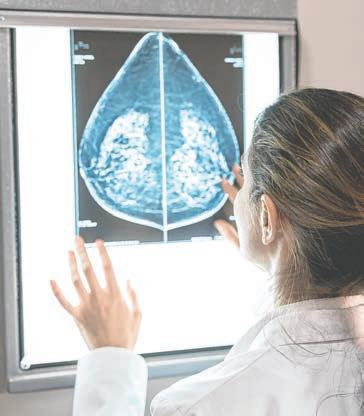

Breast cancer is one of the most prevalent and life-threatening forms of cancer affecting women worldwide. Over the years, significant advances in breast cancer screening have played a pivotal role in early detection, improving outcomes and saving lives.

For decades, mammography has been the cornerstone of breast cancer screening. This X-ray imaging technique captures detailed images of breast tissue, enabling the early detection of tumors long before they become palpable. Traditional 2D mammography has been instrumental in reducing breast cancer mortality rates.

Recent advancements have led to the widespread adoption of 3D mammography, also known as tomosynthesis. This technology captures multiple X-ray images from various angles, reconstructing a 3D image of the breast. It offers several advantages over traditional 2D mammography:

Improved Accuracy: 3D mammography reduces false positives and false negatives, resulting in fewer unnecessary follow-up tests and a higher rate of early cancer detection.

Enhanced Visualization: It provides clearer images, particularly for women with dense breast tissue, making it easier to detect small tumors.

Reduced Callbacks: With improved accuracy, fewer women are called back for additional imaging, reducing anxiety and healthcare costs.

Digital Breast Tomosynthesis (DBT) is a refinement of 3D mammography that further enhances image quality. DBT captures images in thinner sections, offering even better visibility and reducing the potential for overlapping tissues that can obscure tumors. This technology has become a standard in breast cancer screening, particularly for women at higher risk.

Breast MRI is another powerful tool in breast cancer screening, especially for women at high risk or those with dense breast tissue. It uses powerful magnets and radio waves to create detailed, cross-sectional images of the breast. While MRIs can be

expensive and require contrast agents, they excel in detecting small tumors and providing valuable information about the extent of disease.

Breast ultrasound is often used as a supplementary screening tool, especially for women with dense breasts or those with inconclusive mammograms. It uses sound waves to create images of breast tissue. Advancements in ultrasound technology, such as elastography, which assesses tissue stiffness, have improved its diagnostic accuracy.

Artificial Intelligence (AI) and machine learning are game-changers in breast cancer screening. AI algorithms can analyze mammograms and other imaging data with incredible speed and accuracy. They can assist radiologists in identifying potential abnormalities, leading to earlier and more accurate diagnoses.

Advances in risk assessment models allow healthcare providers to tailor screening

recommendations based on a woman’s individual risk factors. These models consider factors like family history, genetics and lifestyle to determine the most appropriate screening approach. High-risk women may benefit from more frequent or intensive screening, such as MRIs or genetic testing.

Researchers are continually exploring innovative ways to detect breast cancer through blood tests and biomarkers. Liquid biopsies, which analyze circulating tumor DNA, RNA or proteins, offer a less invasive and potentially more accurate method for detecting cancer and monitoring treatment response.

Thermography is a non-invasive imaging technique that measures the heat emitted by breast tissue. Although it’s not a primary screening tool, it has gained attention as a complementary approach for early detection. Some advocates suggest that it can identify temperature changes associated with breast cancer. Its role in breast cancer screening is still a subject of ongoing research and debate.

There has been a shift toward patient-centered care and shared decision-making in breast cancer screening. Women are encouraged to actively participate in their healthcare decisions, discussing their preferences and risk factors with their healthcare providers. This approach ensures that screening recommendations align with each woman’s unique needs and values.

While these advances in breast cancer screening have significantly improved early detection and outcomes, challenges persist. Issues like overdiagnosis, false positives and healthcare disparities continue to be areas of concern. Researchers are also exploring emerging technologies like molecular breast imaging and contrast-enhanced mammography to further enhance screening capabilities.

The landscape of breast cancer screening has evolved dramatically, with technological innovations, risk assessment models, and patient-centered care taking center stage. These advances empower women and their healthcare providers to make informed decisions, detect cancer at earlier stages, and ultimately save lives. As research continues and technology evolves, the future of breast cancer screening holds the promise of even greater precision and effectiveness in the fight against this disease. Regular screening and early detection remain crucial, offering the best chance for successful treatment and improved outcomes.